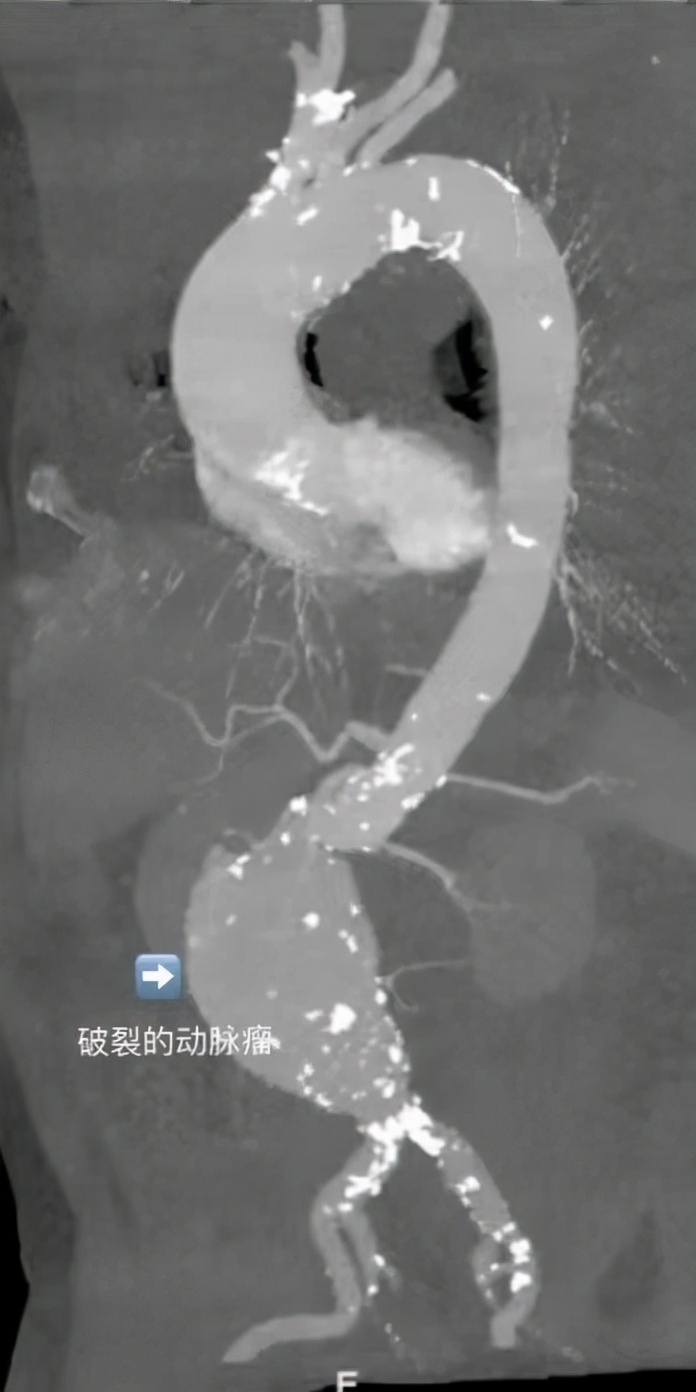

CTA血管造影显示腹主动脉瘤已出现破裂。刘冰教授介绍,动脉瘤素有不定时*破爆**的“血*弹炸**”之称,一旦破裂后不经及时救治,患者将会因大出血而亡。当彭先生被转入血管外科后,值班医生刘鑫禹对彭先生进行血压监测观察病情进展,同时联系血管外科主任刘冰教授及副主任孙庆峰副教授。

刘冰教授,孙庆峰副教授、魏争副教授会诊讨论认为,腹主动脉瘤直径、瘤体形态及累及脏器,瘤颈6mm不适合常规腔内微创手术;且患者84岁高龄,心肺功能较差,也不适合传统开刀手术。微创腔内修复术+右肾动脉烟囱术+瘤腔栓塞术,对于患者是个体化最佳医疗方案,但手术难度和风险则需医生团队来承担。